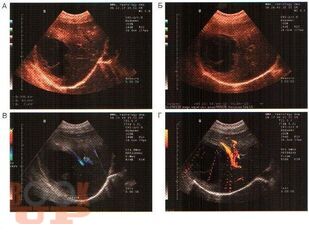

В практическом руководстве отражены вопросы ультразвуковой диагностики доброкачественных, злокачественных опухолей печени, поджелудочной железы, метастатического поражения печени, пороков развития, заболеваний гепатопанкреатодуоденальной зоны. Практическое руководство предназначено для специалистов лучевой диагностики, хирургов, онкохирургов.